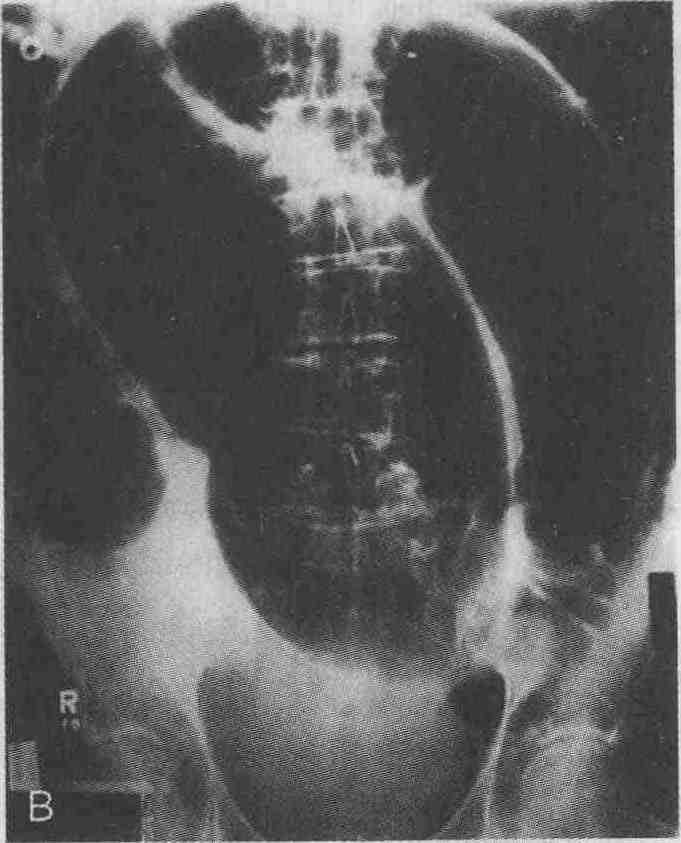

А. Заворот слепой кишки. Расширенная,

на позвоночнике. В. Расширенная петля сигмовидной кишки при ее завороте